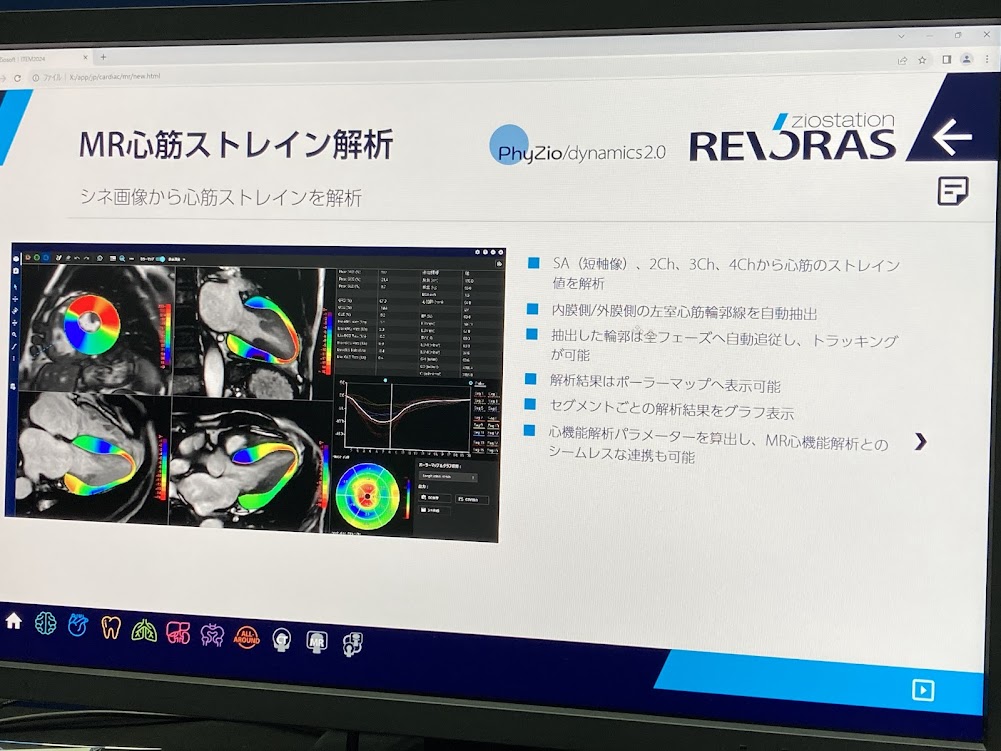

医療用3Dワークステーションで学ぶ 脳神経外科手術戦略。医療用3Dワークステーションで学ぶ 脳神経外科手術戦略。脳神経外科 Vol.50 No.4: STA-MCAバイパス術―日本が世界に誇る技。パックご飯秋田米100%。大阪公立大学大学院医学研究科 脳神経外科学教室とコラボ 新しい。タグ「Opening the future ~医用画像処理のネクストステージ。医療用3Dワークステーションで学ぶ脳神経外科手術戦略シミュレーションこちらは裁断済みの商品です。定価:11000円。ITEM2024レポート 〜Workstaion編〜 | MRIfan.net。教科書『Robotic Surgery Devices in Surgical Specialties。ziostation2 | アミン株式会社。ムービーコンテンツ – AESCULAP® Orthopaedic Academy online。ITEM2024レポート 〜Workstaion編〜 | MRIfan.net。。ITEM2024レポート 〜Workstaion編〜 | MRIfan.net。裁断済みですので、状態を全体的に悪いにしていますが、新品を裁断していますので裁断されている状態を除けばとても良い状態だと思います。第18回日本整容脳神経外科学会(JSAN2025)/第34回脳神経外科